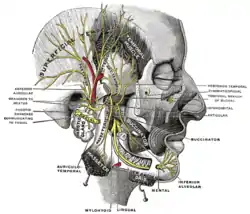

Inferior view of the human brain, with the cranial nerves labelled. Mandibular division of the trifacial nerve.

Mandibular division of the trifacial nerve. Plan of the facial and intermediate nerves and their communication with other nerves.